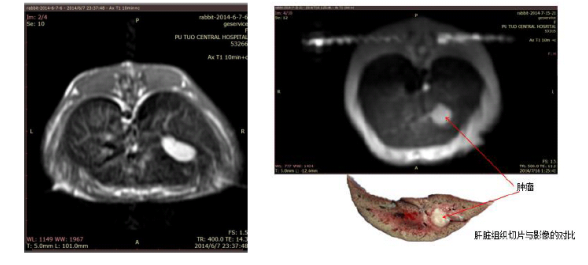

肝脏肿瘤造影: